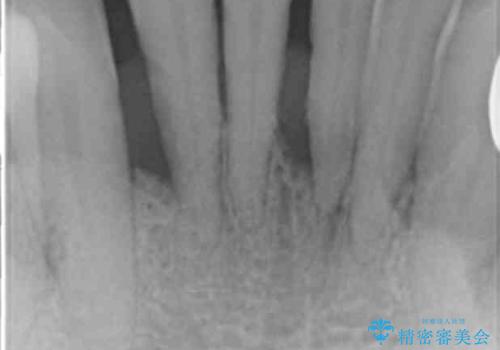

精査したところ、全顎的な重度の歯周病により下顎前歯に激しい動揺を認めました。

再生療法から1年後リエントリー手術により骨の再生を確認し、骨外科処置(骨を平らにして歯周ポケットの根本的な改善を図る処置)を行ったのち、連結補綴を行いました。

骨吸収と動揺が著しい前歯1本(左下1)のみ抜歯しております。

再生療法と骨外科処置により、歯周ポケットは全周2mm以下に改善されました。